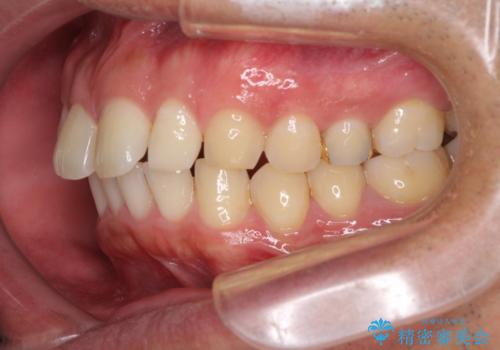

- 上顎前歯の突出感とすきっ歯を気にして来院された患者様です。

奥歯の咬み合わせを見ると、下顎に対して上顎が前方に位置していたため、補助装置により上顎歯列全体を後方に移動させ、その後インビザラインにて歯列全体を整えることとしました。